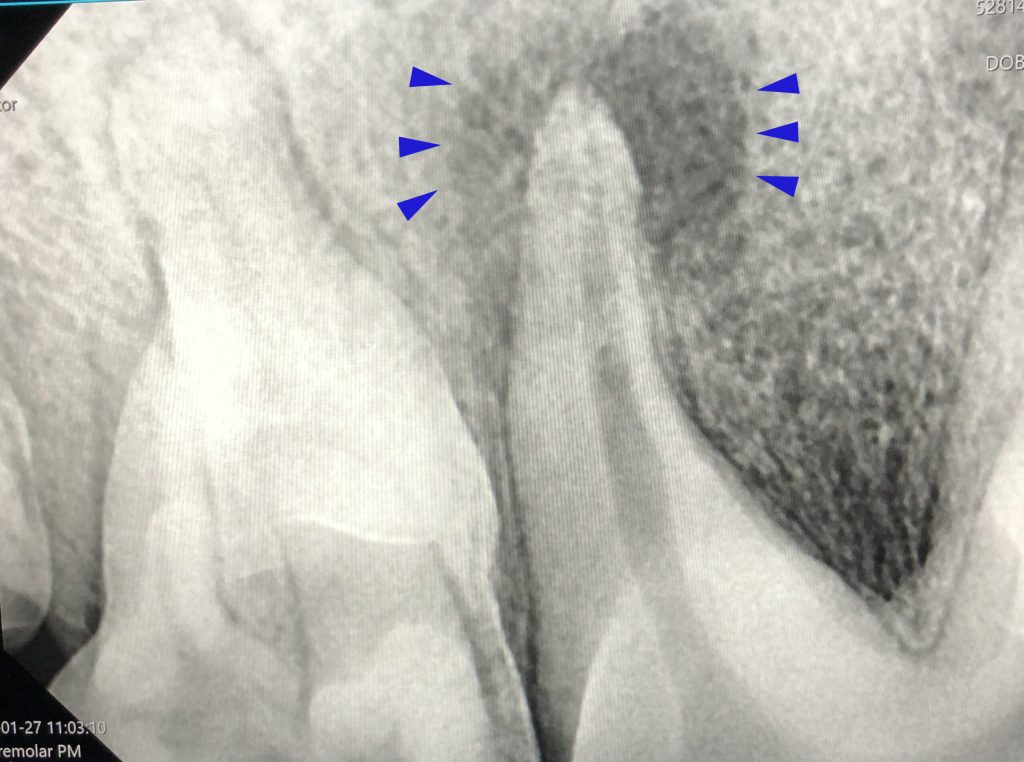

Diagnostiek

Het stellen van een diagnose kan soms net spoorzoeken zijn. Soms is het eenvoudig en soms is het lastig.

Onze diagnostische mogelijkheden hebben we uitgebreid door de aanschaf van vele soorten van apparatuur en het volgen van allerlei cursussen.